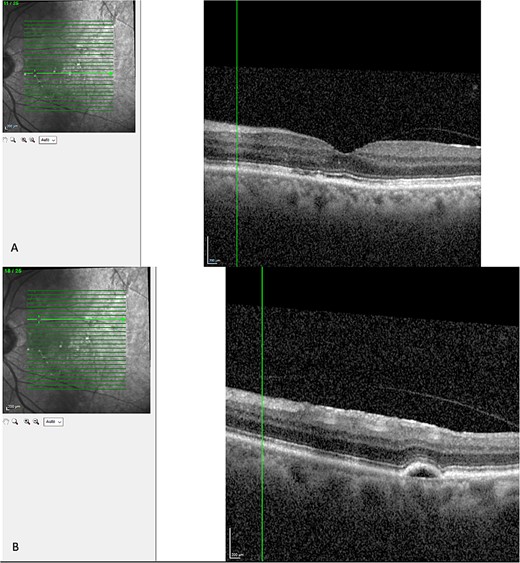

Optical coherence tomography (OCT) demonstrated an atrophied right macular. Whilst the left eye showed a thickened choroid, multiple pigment epithelial detachments (PED), subretinal fluid and intraretinal fluid nasally. This is shown in Figs 2 and 3.

OCT of left eye – showing IRF and pigment epithelial detachment.

The diagnosis of CSCR was made by the patient’s ophthalmologist, meeting diagnostic criteria as seen in Table 1. The patient meets major criteria with an OCT showing serous retinal detachment, and RPE alterations seen in Figs 2 and 3, respectively. Figure 2 displays a subfoveal choroidal thickness of 454 μm meeting the minor criteria.